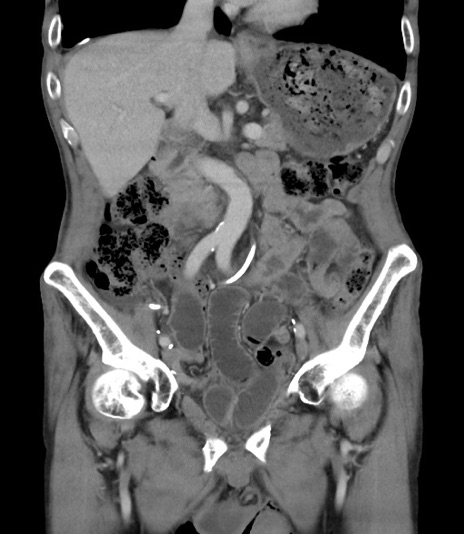

【症例】 70歳代男性

【主訴】右鼠径部腫瘤、疼痛

【現病歴】本日朝より上記主訴あり、受診。

【既往歴】膀胱癌にて膀胱全摘、両側尿管皮膚瘻

【データ】WBC 5600、CRP 0.56